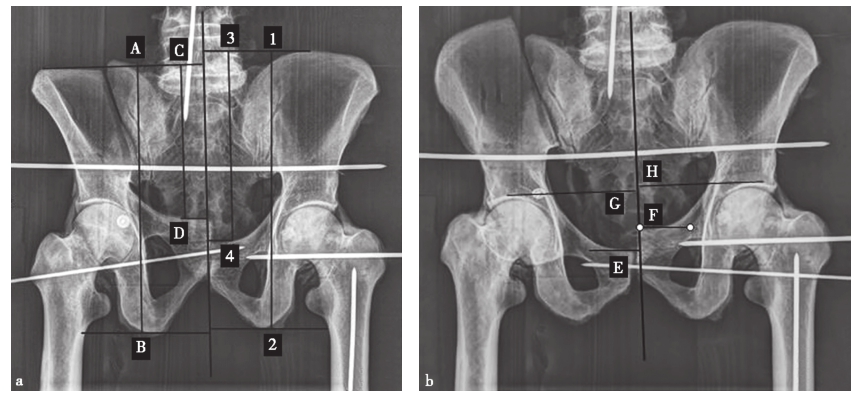

在常规的X线检查中,一些细微的失稳是无法观察到的,只有通过特殊的检查方法才能识别。Sagi等术前在麻醉下对68例骨盆后环的不完全损伤(OTA 61-B型)进行X线和CT检查。他们认为在麻醉下进行的动态应力透视检查显示,50%的前后挤压型(anteroposterior compression,APC)Ⅰ型损伤、39%的APC Ⅱ型损伤和37%的侧方挤压型(lateral compression,LC)Ⅰ型损伤都有隐性失稳(图2-12)。

在骨盆骨折分型系统中,冠状面的垂直位移和水平面中的旋转位移易用X线透视和CT成像来体现。然而,在常规X线和CT扫描成像中却难以观察到骨盆骨折矢状面(屈曲和伸展)的旋转位移。Shui等对8具尸体进行骨盆截骨术以模拟骨盆前环和后环损伤,然后在不同角度测量放射学数据。根据尸体模型的测量结果得出,主要是通过测量髂嵴顶部到坐骨结节最低点或耻骨结节的距离来确定矢状面旋转位移(图2-13)。

图2-12 骨盆后环的不完全损伤影像

a.骨盆正位X线片示APC Ⅰ型损伤;b.CT扫描显示无明显骶髂前韧带损伤;c.外部旋转应力下透视显示为耻骨联合分离> 2.5cm的旋转不稳定型,即APC Ⅱ型损伤;d.对隐匿性APC Ⅱ型损伤的内固定术后。

图2-13 骨盆屈曲(10°)位(图a)和伸展(10°)位(图b)的前后位X线片

a.A-B和1-2分别为骨盆骨折侧和正常侧从髂嵴顶到坐骨粗隆的最低点的垂直距离;从髂嵴顶部到耻骨结节对骨盆骨折侧或骨盆正常侧分别做垂线C-D和3-4;b.E-F为双侧耻骨结节的上升或下降距离;G-H为双侧髋臼顶点的上升或下降距离,即为骨盆矢状面旋转移位的距离。